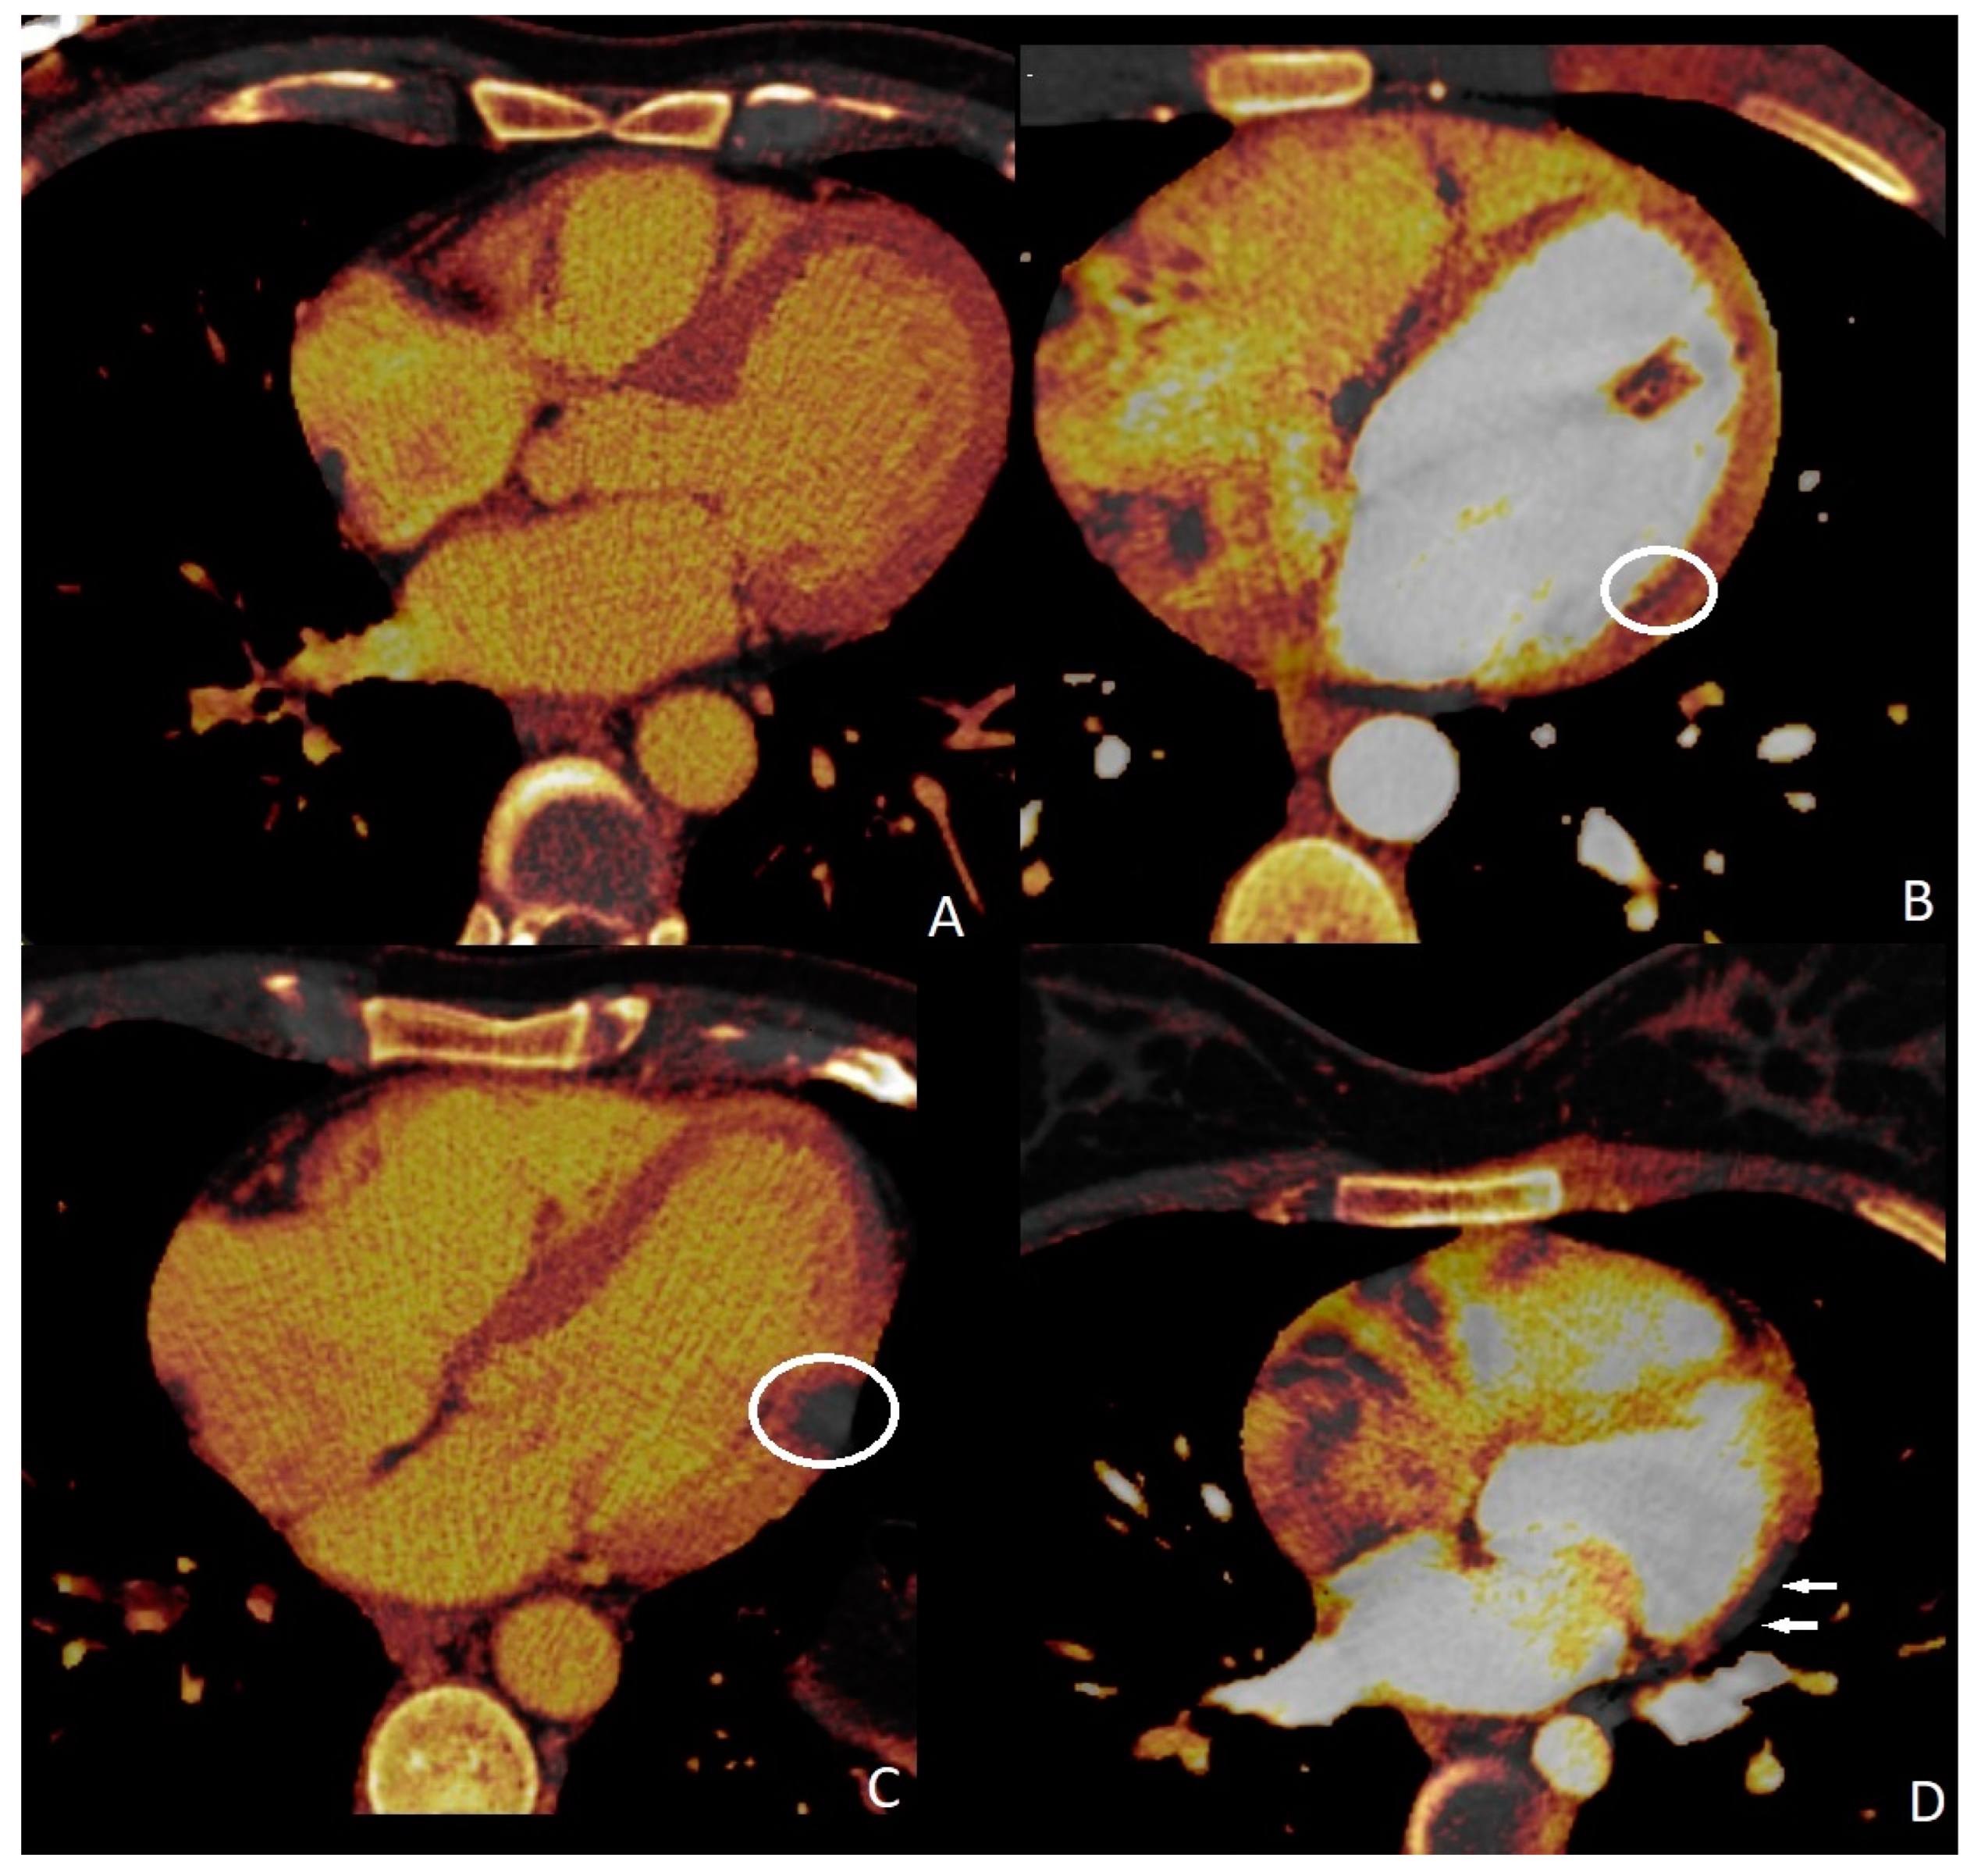

In 13 cases, myocardial perfusion deficits (PD) were identified (13/211, 18%). Cardiac magnetic resonance imaging and myocardial perfusion scintigraphy confirmed the presence of these myocardial PDs. Four of them were associated with substantial obstructive coronary artery disease. Myocardial perfusion abnormalities were observed to be associated with myocarditis in 9 individuals; however, finally, 13 patients were diagnosed with myocarditis (5 of them were identified with COVID-19-associated myocarditis, while the remaining 8 were diagnosed with nonspecific viral myocarditis). We could not define any myocardial PD in four of the myocarditis cases. Sensitivity, specificity, and positive and negative predictive values of quadruple-rule-out CT for myocarditis were 69.2% (95% confidence interval [CI] 65–74%), 100% (95%CI 96–100%), 100% (95%CI 96–100%), and 93.6% (95%CI 90–97%), respectively. Cohen’s coefficient of variation (ĸ value) for the presence of myocardial PD was 0.73 (substantial).

Perfusion deficits were found on DECT iodine map images with a subendocardial (n = 4, 30.7%), subepicardial (n = 7, 53.8%), and transmural (n = 2, 15.3%) anatomical location within the left ventricular wall (Figure 3). Subendocardial involvements were found in the patients who had obstructive CAD, and PDs correspond to associated coronary artery territories. Subepicardial and transmural PDs did not correspond to any coronary artery territories. ROI was used to measure the perfusion deficit and normal areas on the iodine map images on DECT. The mean value of the perfusion deficit areas was 162.13 ± 21.31 HU (range, 45–294), while that of the normal areas was 50.11 ± 9.32 HU (range, 23–91).

Figure 3.

Myocardial perfusion maps. Normal (A) perfusion image, subendocardial ((B), circle), transmural ((C), circle), and subepicardial ((D), arrows) perfusion deficits.